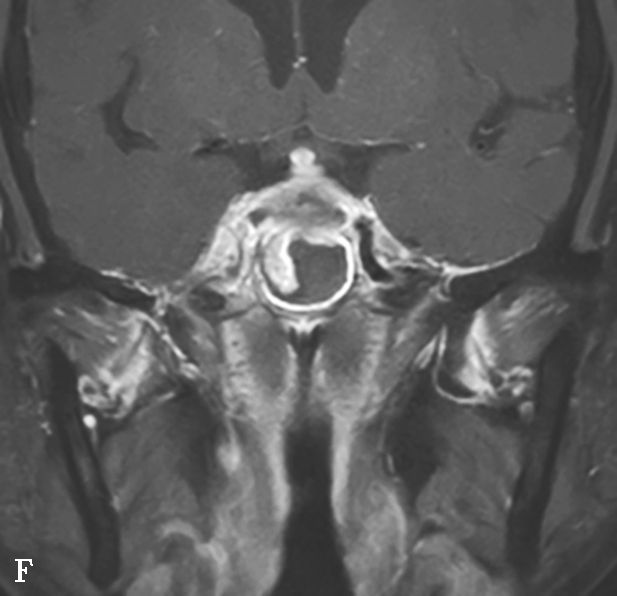

图1-3-20 慢性鼻窦炎

A~C.横断面、冠状面及矢状面CT平扫,示右侧额窦、上颌窦黏膜增厚,窦腔内可见软组织密度影,窦口鼻道复合体狭窄,右侧上颌窦窦壁骨质增生硬化、肥厚;D~F.同一患者横断面MR T 2 WI、T 1 WI及横断面增强T 1 WI,示右侧上颌窦黏膜增厚,呈T 1 WI等信号、T 2 WI高信号影,增强扫描示右侧上颌窦黏膜线样强化